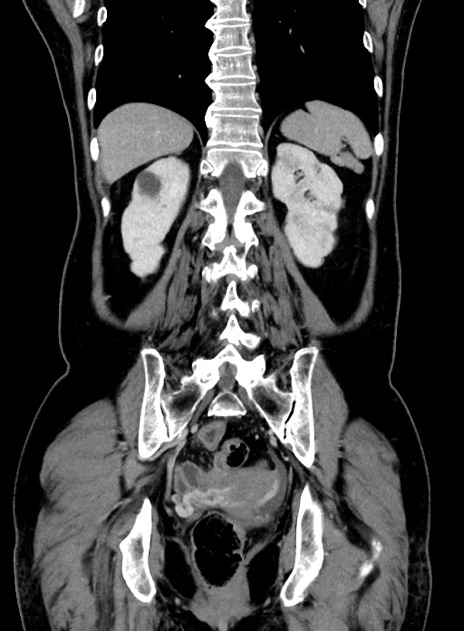

横断像

【症例】 60歳代女性

【主訴】むかつき、みぞおちの痛み

【現病歴】3日前よりむかつきがあり、食事がとれない。

【既往歴】糖尿病

【身体所見】発熱なし、心窩部圧痛軽度あるも、腹膜刺激症状なし。

【データ】WBC 7400、CRP 1.92